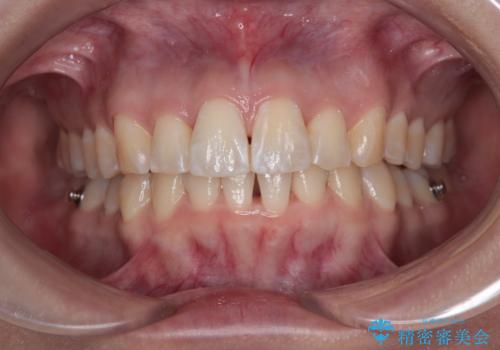

前に飛び出して目立っている前歯を整える インビザライン矯正治療

- 前方に主張した前歯2本を気にして来院された患者様です。

下顎前歯がデコボコしており、その影響で上顎前歯が前方に押し出されている状態でした。

口元が閉じにくいという印象はなかったため、非抜歯矯正にて歯列を整えていくこととしました。

上下左右の親知らずを抜歯し、上下ともに歯列を後方と側方に拡大し、口元を突出させることなくデコボコを解消することとしました。

前歯の形が台形であり、歯列が整ったところでブラックトライアングルが目立つ仕上がりとなったため、IPR(歯と歯の間を削る処置)によって歯の形態を修正し、隙間の目立たない歯列に仕上げることができました。